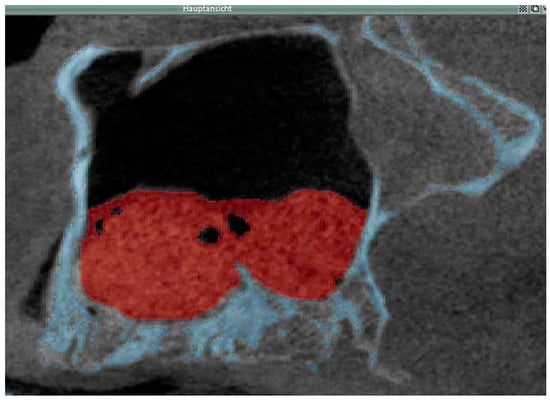

2.3.1. Cone Beam CT

2.3.2. Data Transfer, Analysis and Volume Determination

3.2. Radiological Results